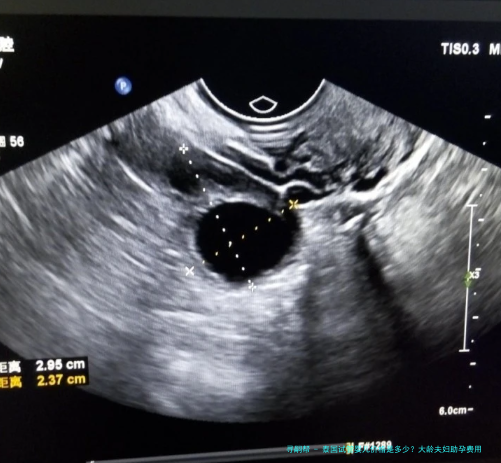

1.术前检查费用:平常在5000-8000元人民币左右。这囊括男女两边的身体检查,如血常规、激素水平、传染病筛查、B超、精液解析等,旨在评估体质状况,排除不利因素。

3.取卵及胚胎培育费用:大约在2.五万-3.5万元元钱。这囊括了取卵手术费、麻醉费、胚胎培育费(常规培养至第3天或第5天囊胚)、显微受精技术(卵胞浆内单精子注射)费用等。如果选择泰国Jetanin生殖医学中心,其技术和服务平常包含在内。